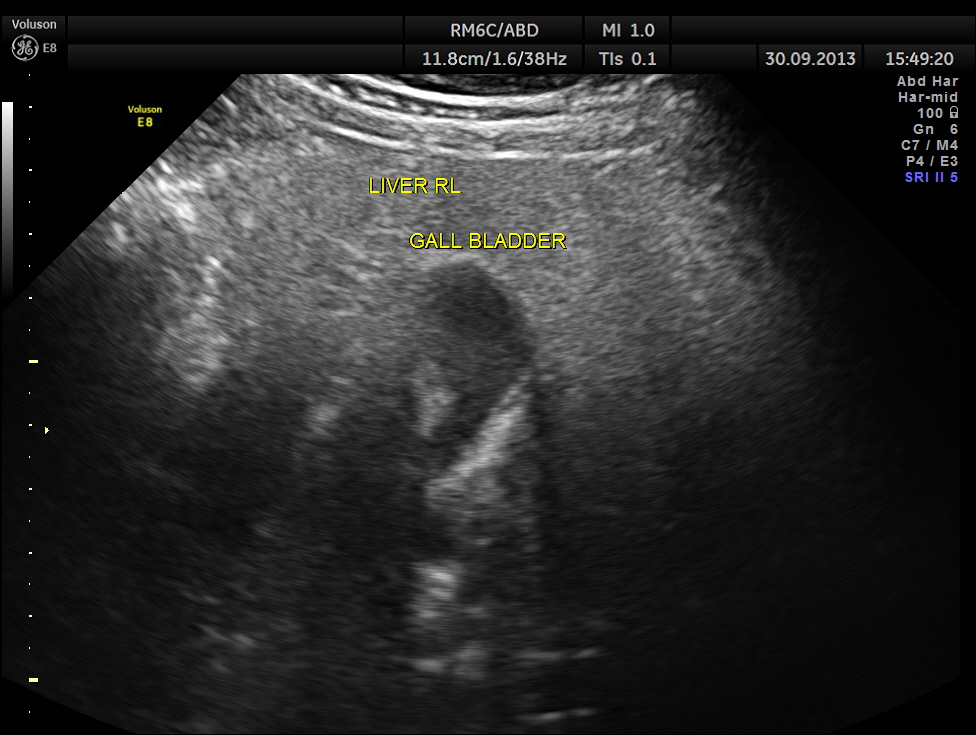

This was a 57 year old gentleman , with complaints of difficulty in passing urine and dysuria of 1 month duration.

His upper abdominal scan was normal . His left kidney was normal.